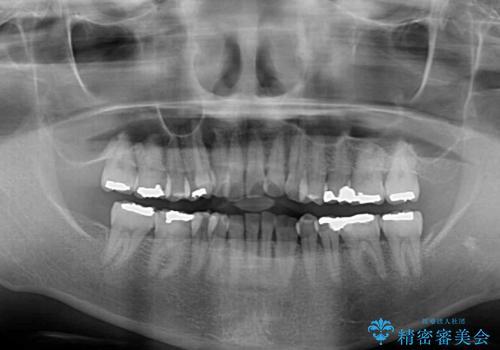

- 長年前歯の歯並びで悩んでいるとのことで来院された患者様です。

機能的なことを考えると八重歯となっている犬歯は抜歯せず、歯列を改善することが望ましいとされますが、数十年もの間犬歯がない咬み合わせで問題なく過ごしてきたため、八重歯を抜歯することで、手っ取り早く歯列を改善することとしました。

また、当初は予定しておりませんでしたが、歯列が整ったことで前歯の歯の色や形が気になり、矯正治療後にオールセラミッククラウンにて補綴治療することとしました。